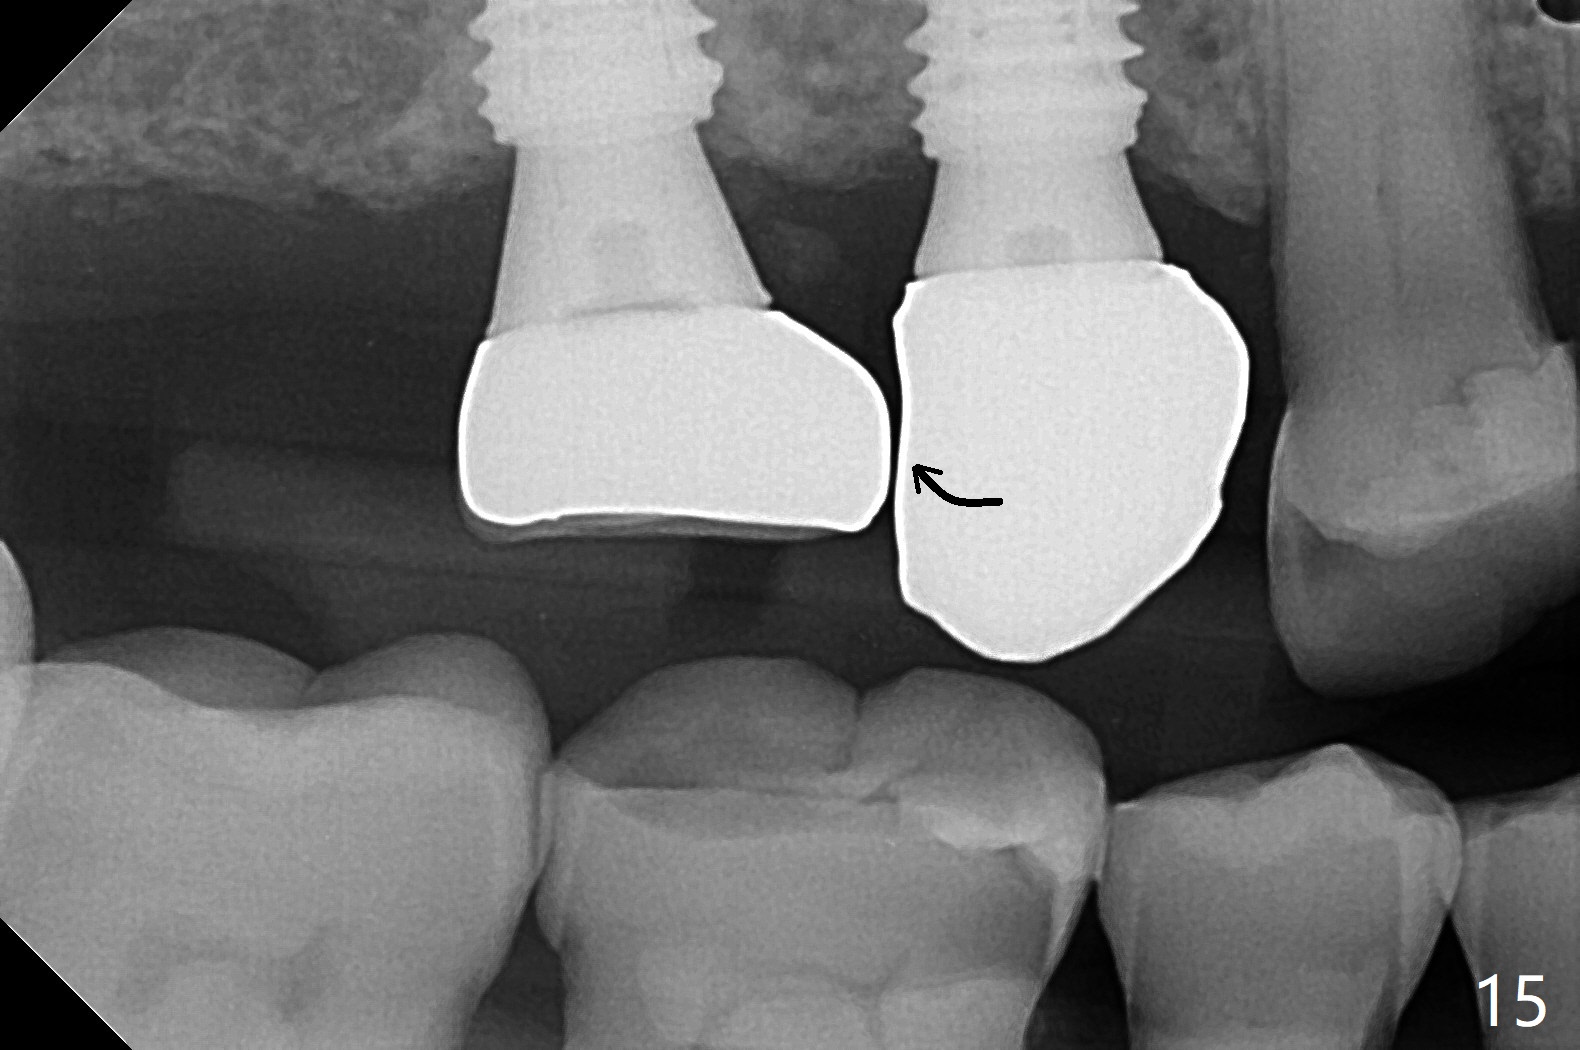

Osteotomy at #3 is performed last (Fig.1,2); as planned, a 4 mm cortical tap is used with guide for sinus lift. Unfortunately the sinus membrane is perforated. Implant placement is aborted. Instead Osteogen plug is inserted into the osteotomy, which is fixed in place by acrylic extending from the provisional at #4. Osteotomy for #3 implant will be attempted with control of the depth in 4 months. The patient has allergy to Amoxicillin (rash). When switching to Clindamycin, she develops diarrhea and loses 10 pounds. There is no abnormality at the site of #3 or 4 nearly 3 months postop (Fig.3). The next surgery will be most likely conducted without antibiotic 4 months postop. Try to draw blood for PRF. Take PA for #12 and 13 for possible impression. Remove the 3 temporary crowns, seat the guide across the arch and use no-stop fixture mounts at #4, and possibly 12 and 13. Follow the original drill sequence (check perforation after each drill, Fig.11) and use DIONavi sinus approach kit. Also load an appropriate stop for the round bur for sinus lift before hand. Mixture allograft with Metronidazole and PRF. In fact everything goes on as smoothly as planned. Osteotomy at #3 is underprep (3.5 mm in diameter drill instead of 4.0). The sinus floor appears to remain to be absent; 3.2 mm round bur is used for lift, alternating with water pumping. Following insertion of 3 pieces of PRF membranes and Vanilla Graft (Fig.4 *), a 4x10 mm dummy implant is placed. After additional bone graft (Fig.5 *), a final 4.5x7.3 mm implant is placed ~10 Ncm. The implant is placed deeper ~ 1 mm, followed by a 5.5x3 mm healing abutment (Fig.6). The implants at #12 and 13 seem to have osteointegrated (Fig.7). Impression is taken for #4, 12 and 13 with limited vertical space (Fig.8,9). An implant at #14 is being considered. There is faint bone graft around the apex of the implant 4 months postop (Fig.10). The implant sustains 25-30 Ncm torque when a 5.2x4(3) mm cemented abutment is placed. A permanent crown is cemented nearly 5 months postop (Fig.11). For the best cosmetic and masticating results, the occlusal surface should have certain degree of morphology, such as the buccal cusps (Fig.12 white curved lines). The abutment at #3 is placed and torqued to 30 Ncm before re-cementation of the repaired crown (increased occlusal surface contact). In fact the abutment at #4 is incompletely seated with a gap (Fig.13 <). The composite at #5 is dislodged while #3 crown is being repaired (*). The abutment at #4 is loose >1 year post cementation. The abutment remains incompletely seated (gap and longer apical space (double arrows)) when the abutment/crown complex rotates lingual mesiobuccal (Fig.14 curved arrow). Further proximal reduction and lingual rotation distobuccal leads to complete seating (Fig.15). It appears that incomplete seating at #13 is associated with hex mismatch (Fig.16, large apical space), which will be fixed next visit. One week later, the crown and abutment of #4 are seated together after crown repair (Fig.17). Since the abutment margin is subgingival, the crown is cemented, removed with abutment for residual cement removal and reseated with the abutment with torque at 30 Ncm. After this, the crown and abutment of #13 is reseated after mesiobuccal surface is trimmed (Fig.18), followed by pick up impression. A few days later, the crown/abutment are inserted together smoothly, the former cemented and the complex unscrewed for residual cement removal and last torqued at 30 Ncm without any X-ray confirmation.